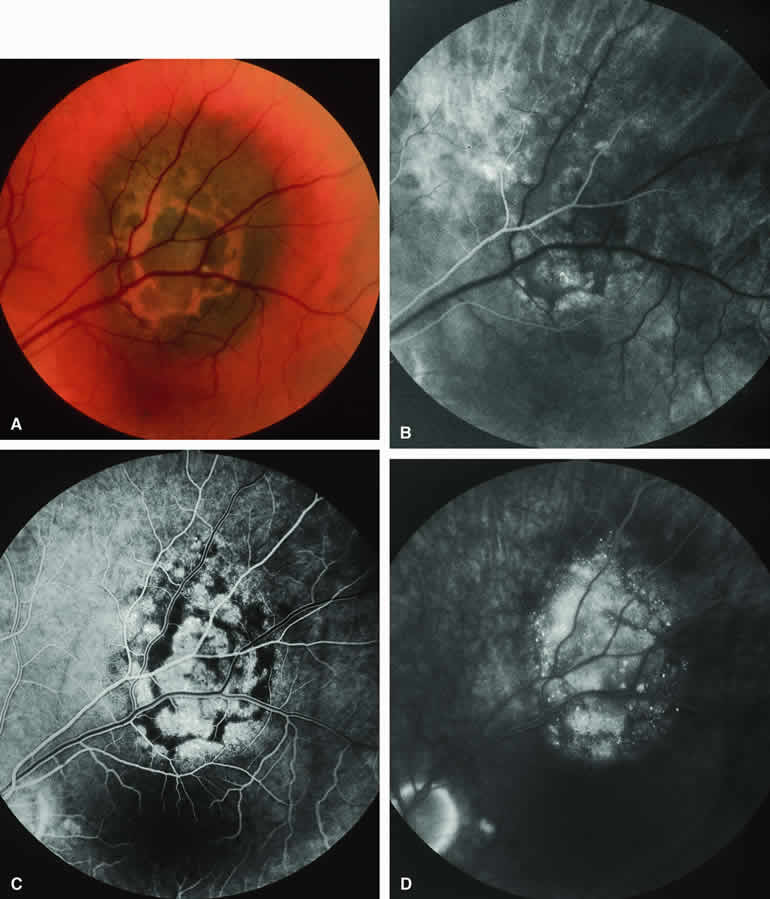

Fig. 1. Typical melanotic choroidal nevus. A. Ill-defined gray-brown macular choroidal lesion with bland surface features. B-D. Fluorescein angiogram of lesion. B. Laminar venous phase frame showing intact retinal vasculature overlying nevus but virtually no hypofluorescence corresponding to choroidal lesion. C. Full venous phase frame showing granular hyperfluorescence corresponding to minor retinal pigment epithelial alterations and drusen on surface of tumor. D. Late-phase frame showing continued hypofluorescence of choroidal lesion with mild staining of surface drusen.

Fluorescein angiography of a typical choroidal nevus with bland surface features (see Fig. 1) shows the entire lesion to be hypofluorescent relative to the adjacent uninvolved choroid throughout the study. No large-caliber choroidal blood vessels are usually identifiable within the lesion. The retinal vasculature overlying the lesion appears well defined and normal on fluorescein angiography.